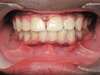

Avant / Après